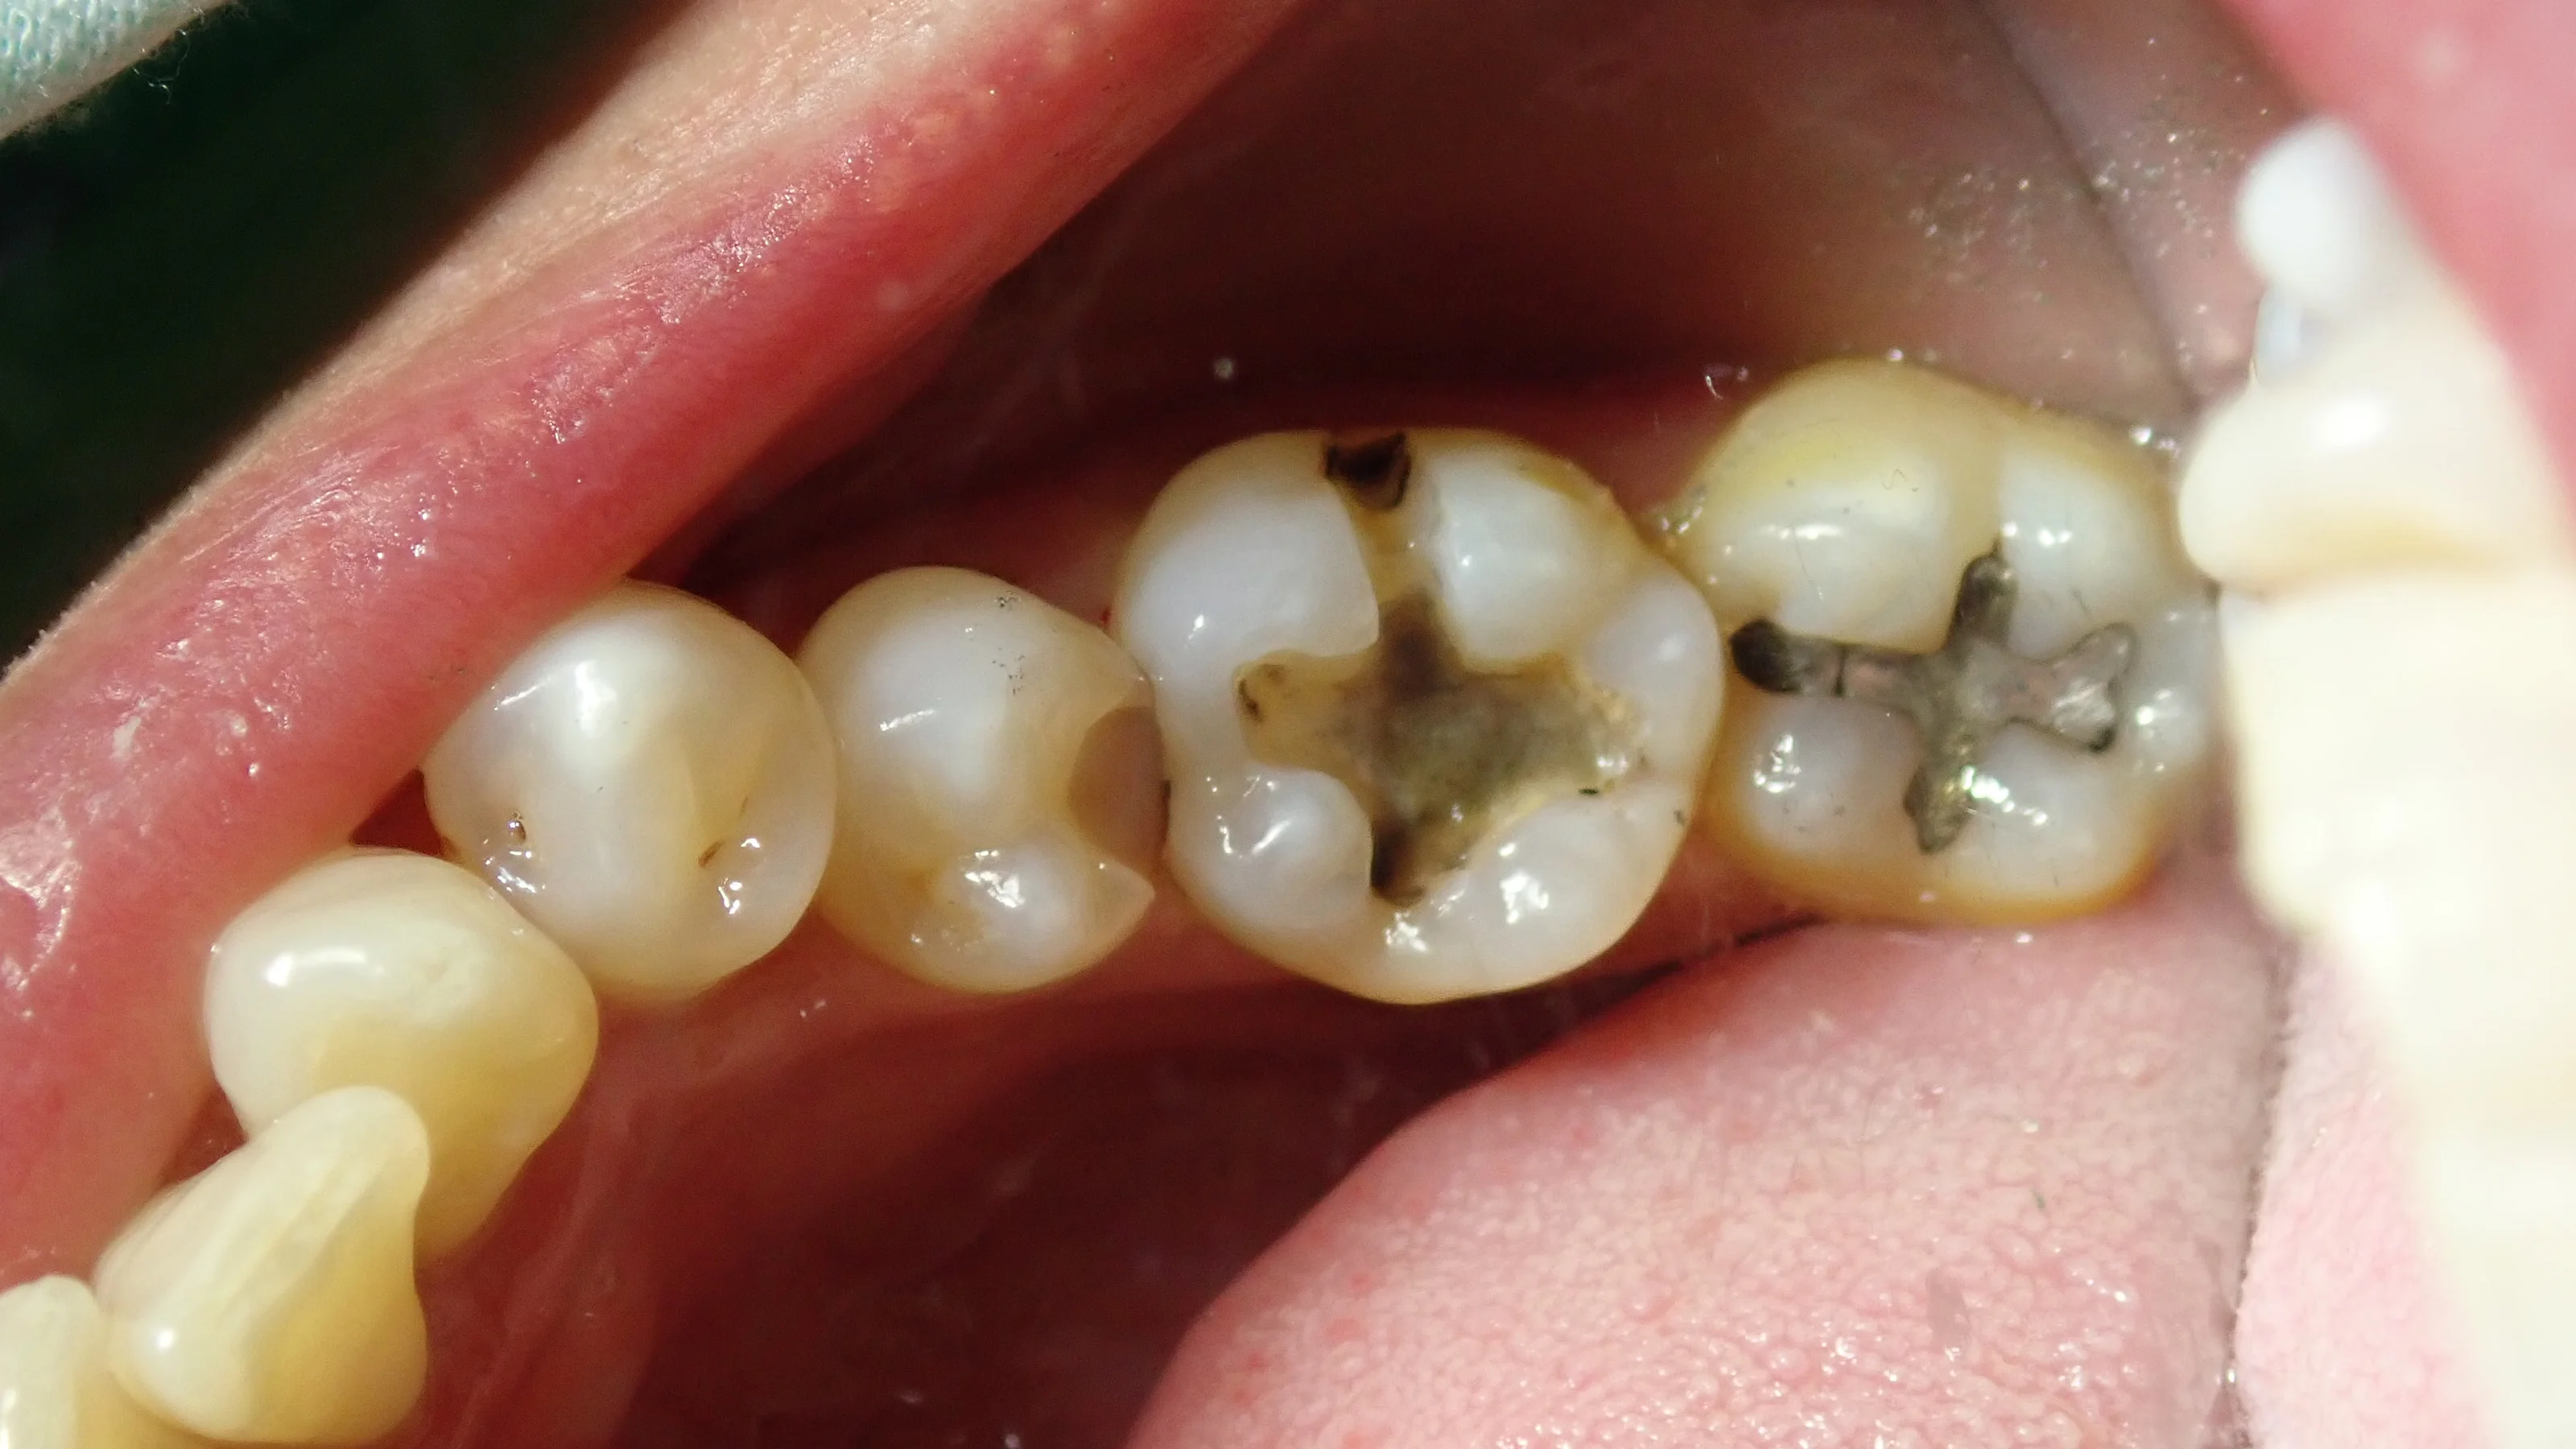

まずは、術前の状態です。

金属の詰め物と、適合のあまり良くない、白い詰め物が入っている場所が今回の治療箇所です。

金属の方は見た目上では虫歯はありませんでしたが、レントゲンにてはっきりと、大きな虫歯になっていたのが確認できました。

詰め物をどちらも除去したのがこちら。

結構黒いのが見えてきたと思います。

手前の、白い詰め物は外していない状況で撮っちゃいましたね。すみません。